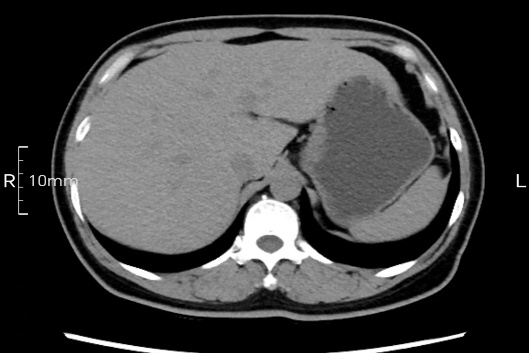

沒禁食,胃內全是食物,導致胃壁顯示不清。